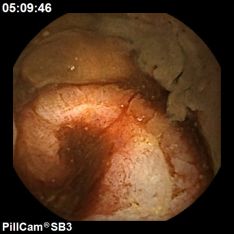

La cápsula endoscópica es una herramienta que se utiliza para examinar de forma no invasiva el tracto gastrointestinal. En la práctica clínica existen dos tipos de cápsulas, la de intestino delgado y la de colon.

El procedimiento es sencillo y ambulatorio, consiste en deglutir el dispositivo que tiene un tamaño similar al de una pastilla/cápsula. Tras la ingestión, la cápsula iniciará la captura imágenes a su paso por el tracto gastrointestinal. En la mayoría de los casos, después de ingerir la cápsula el paciente podrá volver a su domicilio.

Las imágenes capturadas serán transmitidas a unas antenas o sensores que están dentro de un cinturón que portará el paciente junto a una grabadora donde serán almacenadas.

La grabadora se descargará en un ordenador con un software específico que creará un vídeo con las imágenes capturadas. Corresponde posteriormente el médico responsable del procedimiento ver/leer el vídeo y realizar un informe.